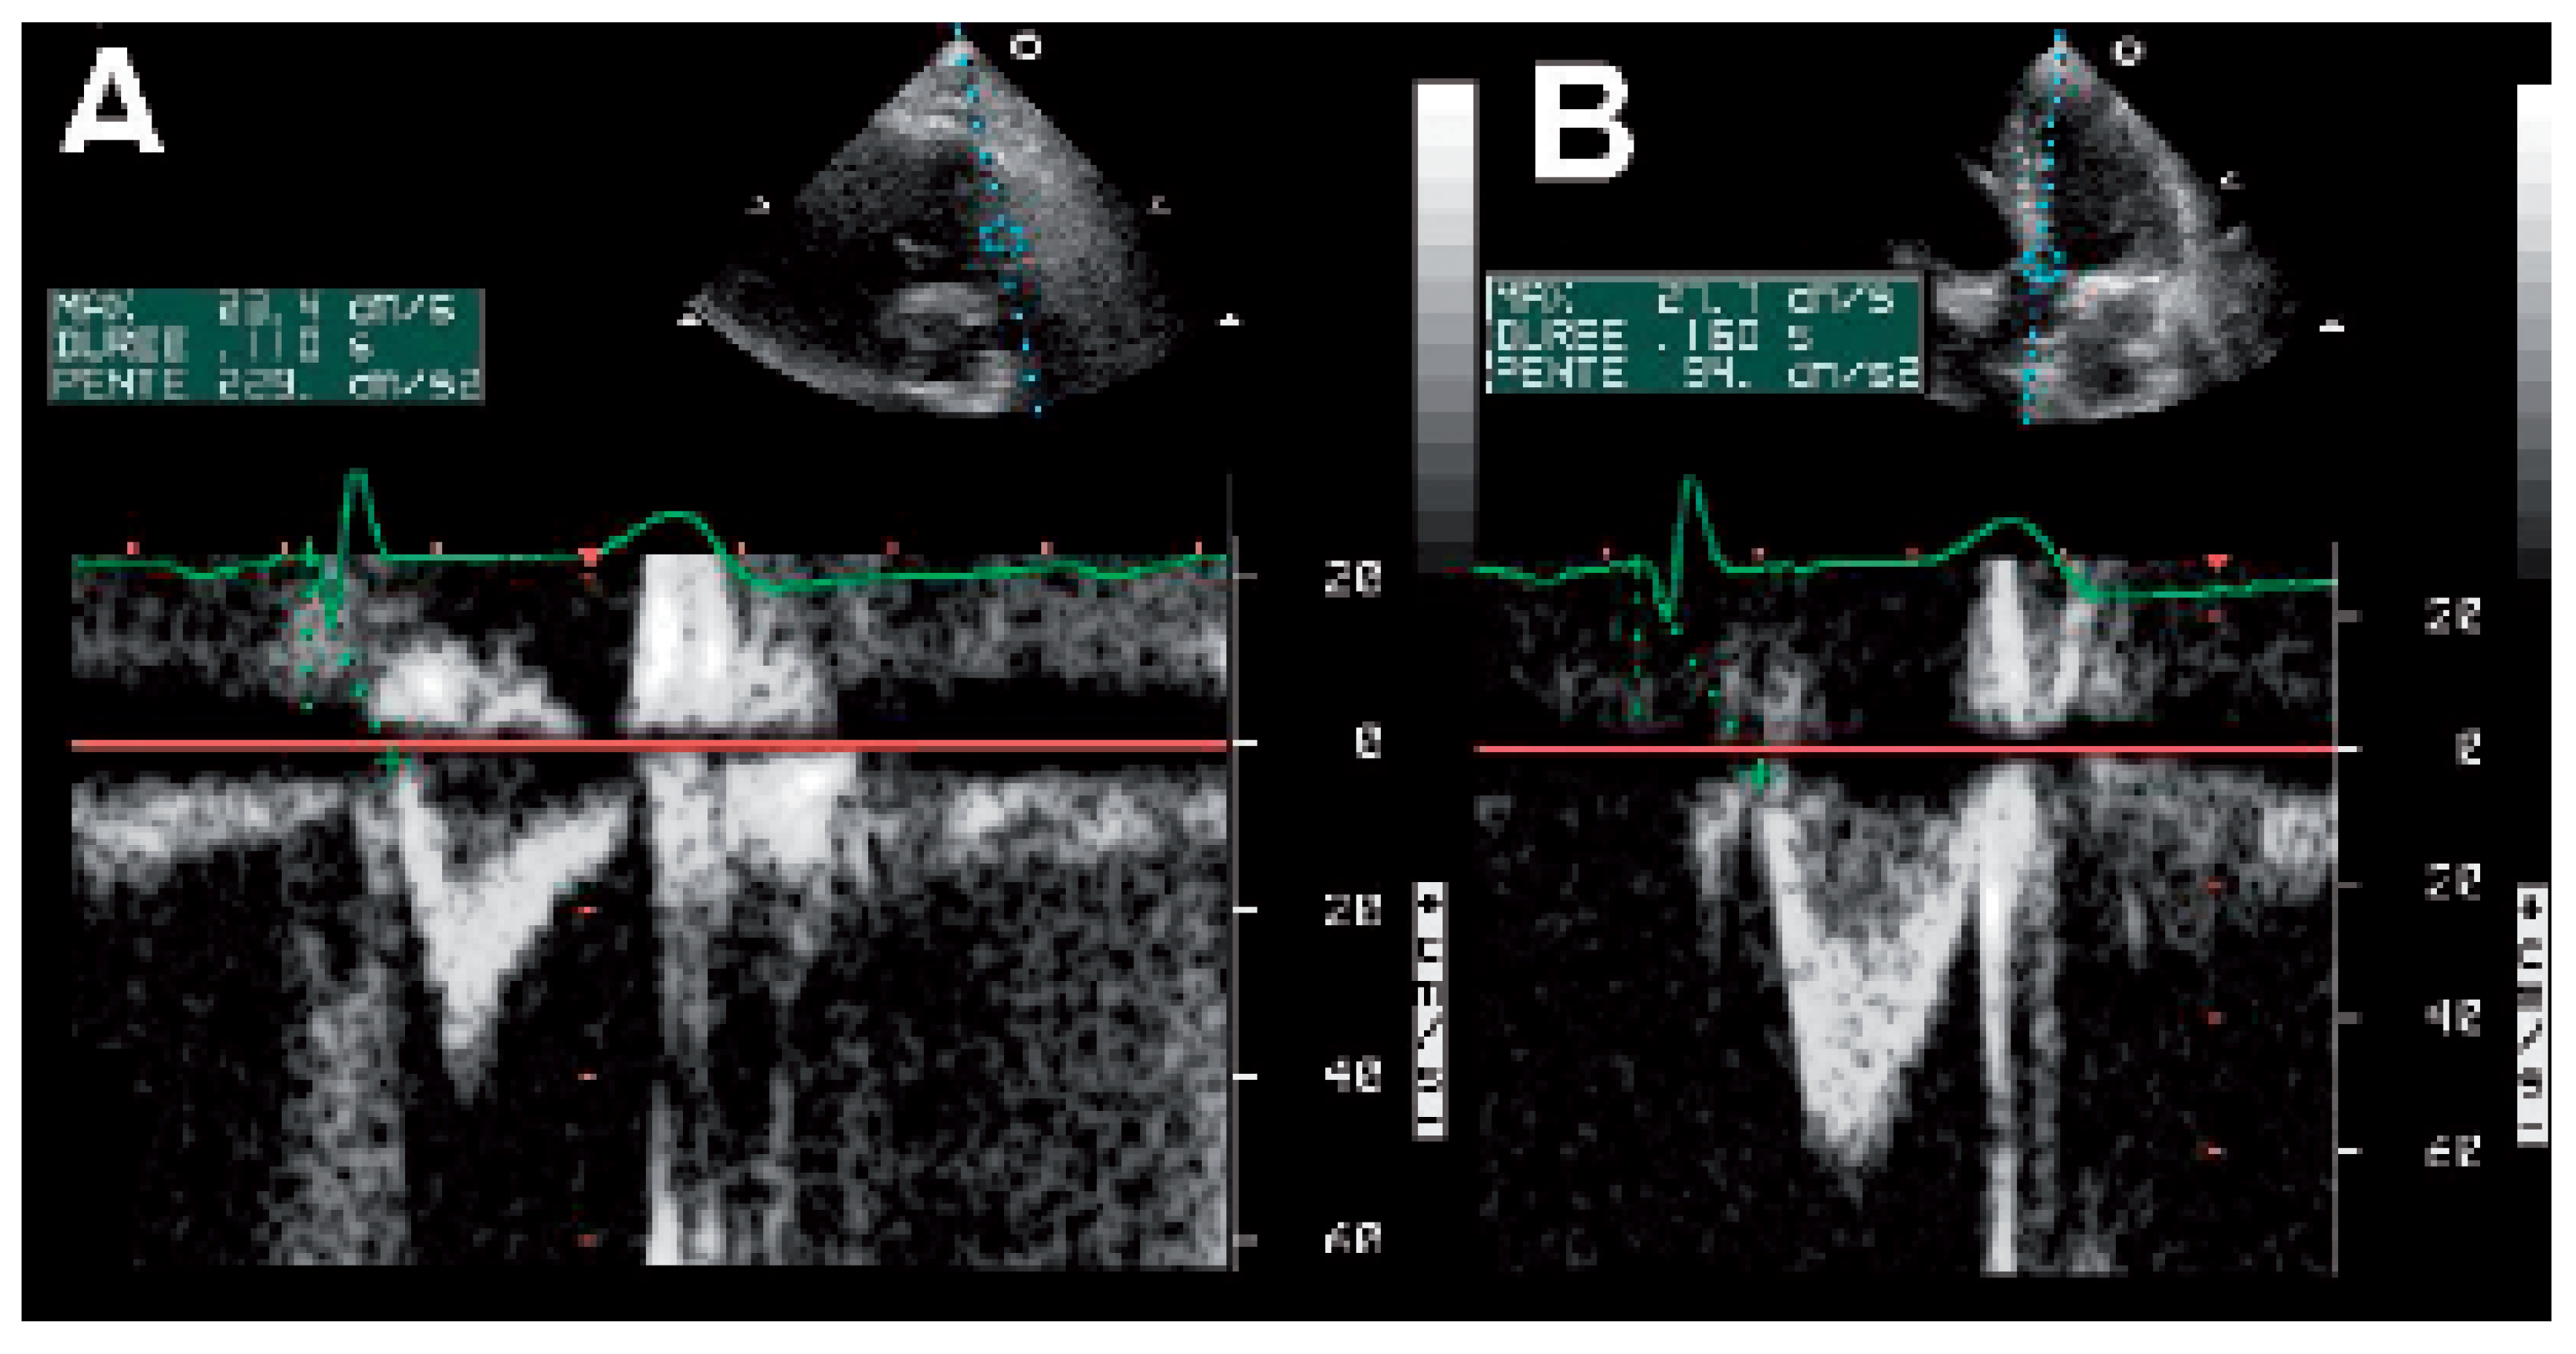

VV interval optimisation